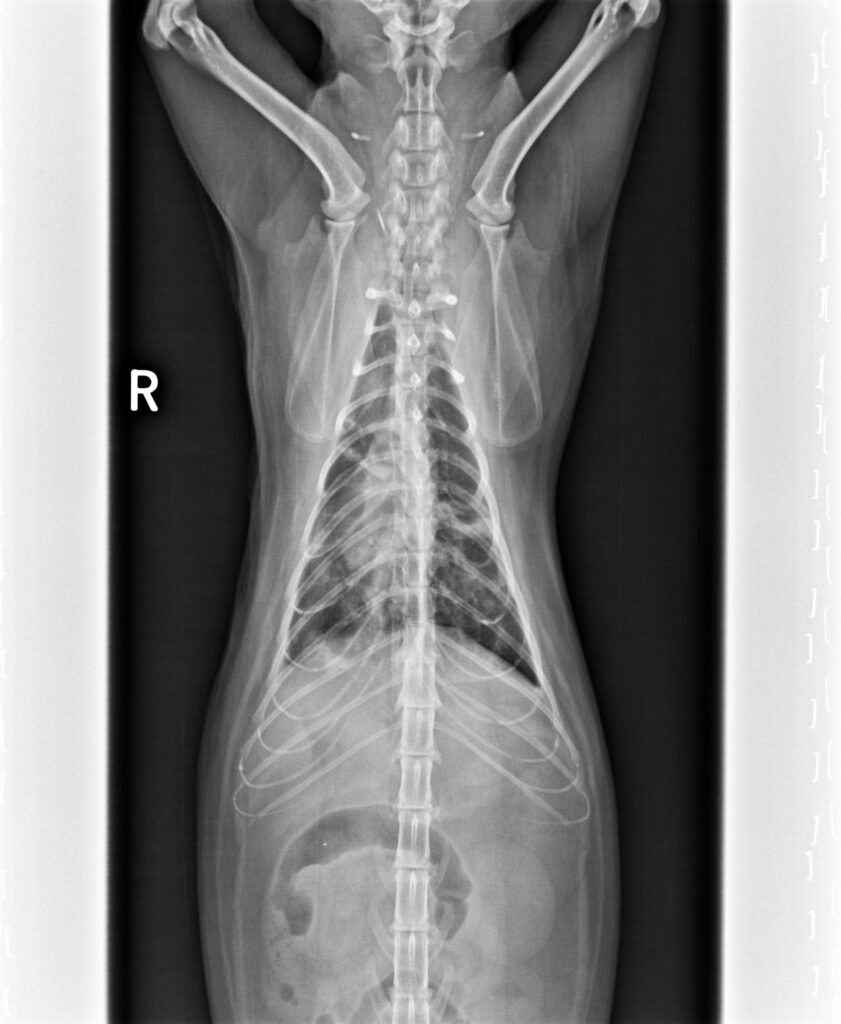

2023/5/11,一位街貓5.3公斤,3歲的橘貓因為很喘被附近的愛心人士帶來就診。愛心人士表示平時橘貓在他們家附近閒晃,他們就是定時餵食飼料,最近沒看到橘貓,再看到橘貓時就是一副很喘的樣子來找他們。愛心人士擔心之餘,經人介紹前來看診;在緊急為橘貓照完X光後,果然是罹患了肺炎。

胸腔X光1-3張見到瀰漫性結節團塊浸潤